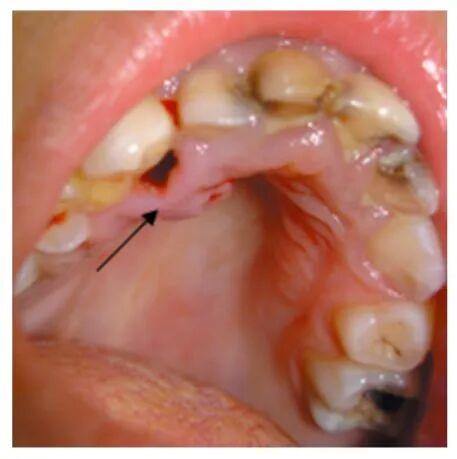

箭头处显示上颚红肿,且右齿的牙龈上有个空洞,蝇蛆就在寄生在此处。女孩的口腔卫生很差,基本上每个牙齿都有龋坏。年仅5岁,就有牙龈炎丨文献[4]